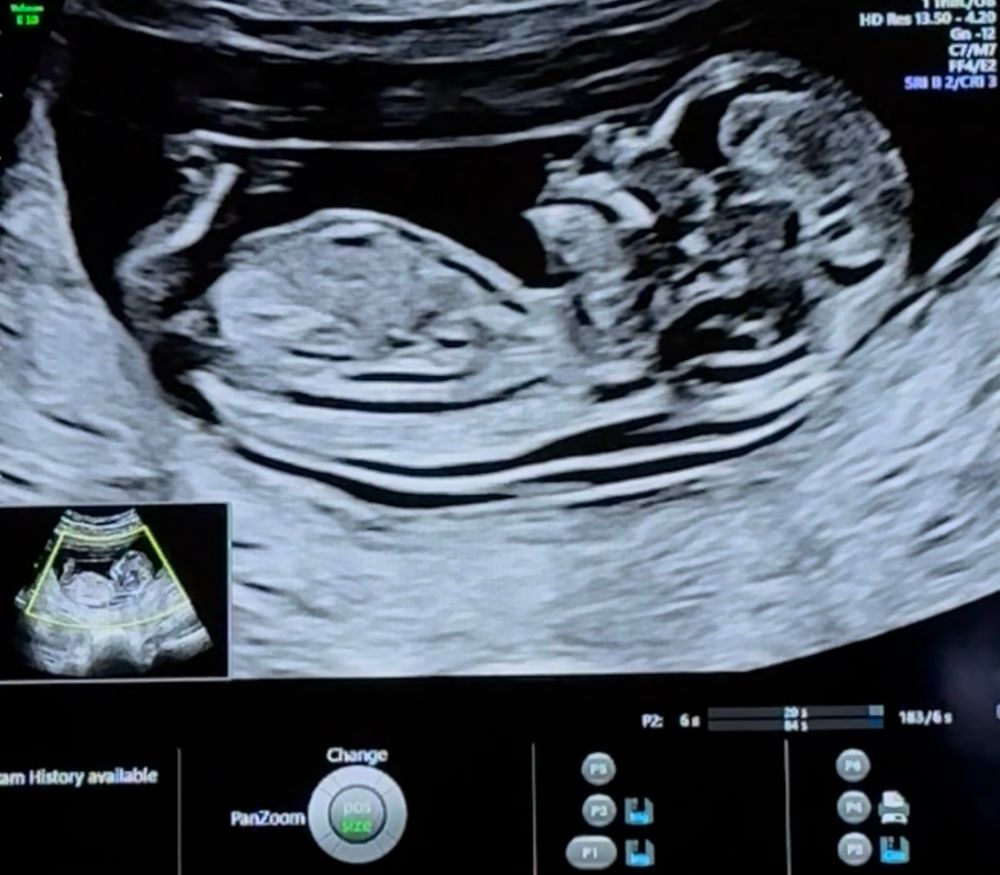

Пол ребенка в 12 недель (половой бугорок), мальчик или девочка?

за ножкой не видно бугорка(

Ножка закрыла бугорок. Сдайте кровь на пол, я вчера сдала (13.3 недель), до скрининга не хотела сдавать

У меня сын на первом скрининге прям писюн показал😃. Думаю девочка.

Вроде как на девочку похоже, у мальчиков бугорок "крючёчком" вверх

Сбоку ножкой закрылся, а снизу на таком сроке не смотрят ☺️